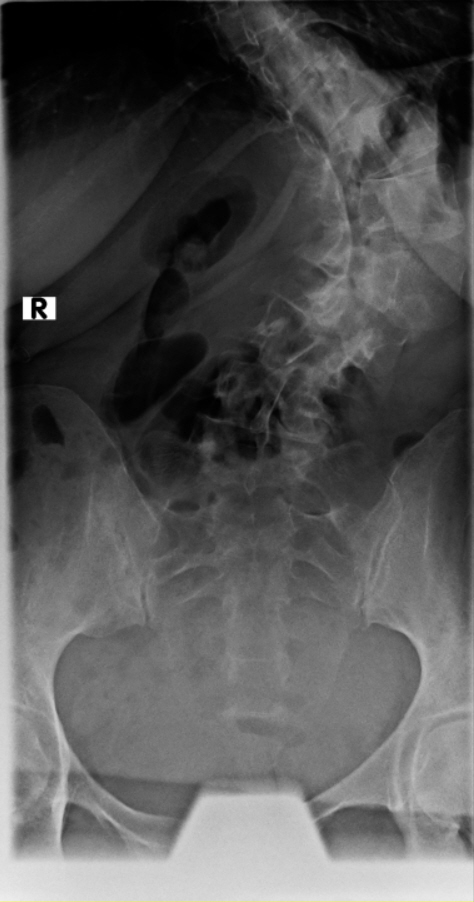

Thorakolumbalskoliose mit aktuellen COBB-Winkeln von 80 und 60 Grad...wenig Schmerzen und daher meistens glücklich

Viele kennen sich aus, daher möchte ich euch meine aktuellen Röntgenbilder nicht vorenthalten und hänge sie unten an.

Ich war beim MVZ Gersthofen, dort wurden die Röntgenbilder gemacht…die massive Verschlechterung war sehr offensichtlich

Dort wurden die Winkel gemessen, unten 80 Grad und oben 60 Grad…eine Verschlechterung von über 2 Grad pro Jahr, wenn man es auf die ganze Zeit berechnet

Die Winkel hab ich nachgemessen, wie der Arzt der Hessing und hier mal als Screenshot